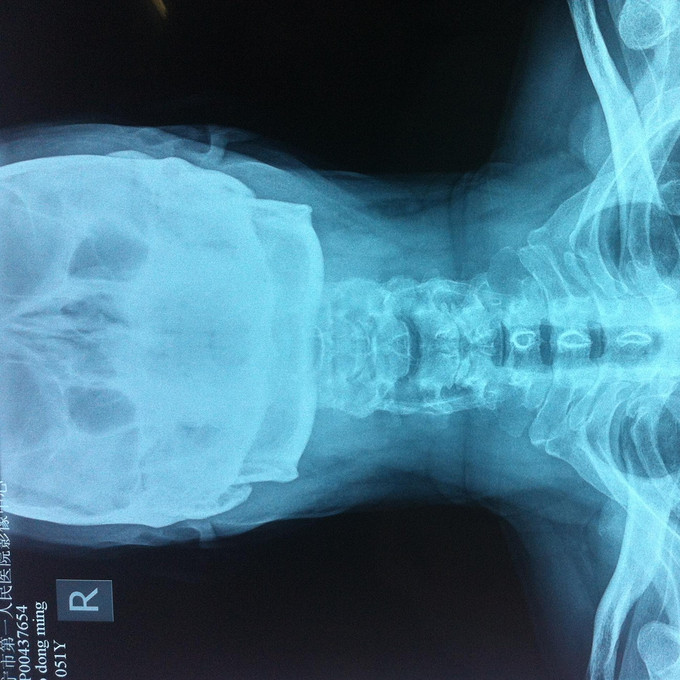

查体:颈后部压痛,颈部活动受限,双侧前臂及手感觉减退,双侧伸腕、伸肘肌肌力4级,双侧霍夫曼综合征阴性,双下肢感觉无减退,双下肢肌张力高,巴氏征可疑阳性,辅助检查: X-ray:劲椎退行性变 CT:颈椎间盘突出,腰5/6 MR:颈椎间盘突出,颈5/6节段明显

诊断:混合型颈椎病 处理: 1、完善相关辅助检查,明确诊断,有无手术指证; 2、完善手术评估,有无手术禁忌,手术风险及并发症; 3、在全麻下行颈椎前路减压,颈5/6椎间Cage植骨融合内固定术